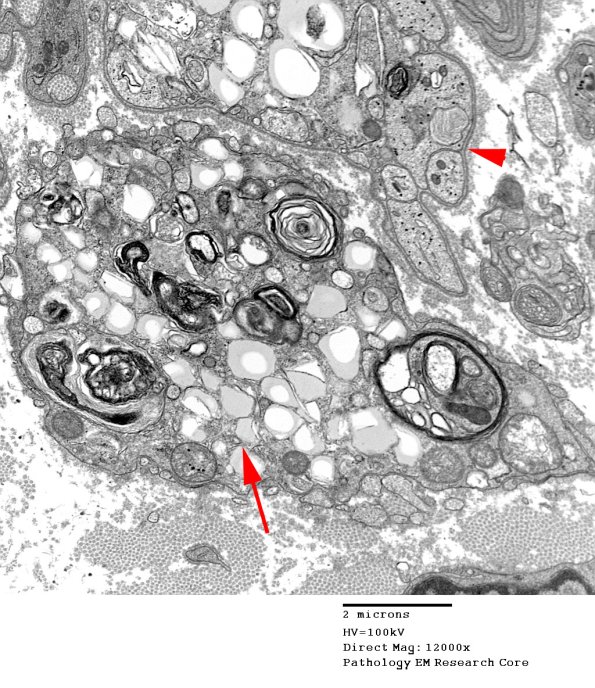

Several magnifications of a Schwann cell (arrowhead) containing myelin debris and vacuoles of neutral lipid with an adjacent macrophage (arrow) containing similar engulfed Schwann cell debris.